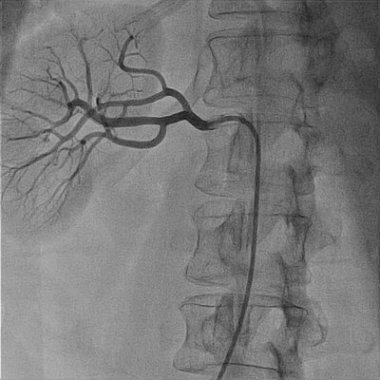

آنژیوگرافی شریان های کلیه

تشخیص دقیق عروق کلیوی